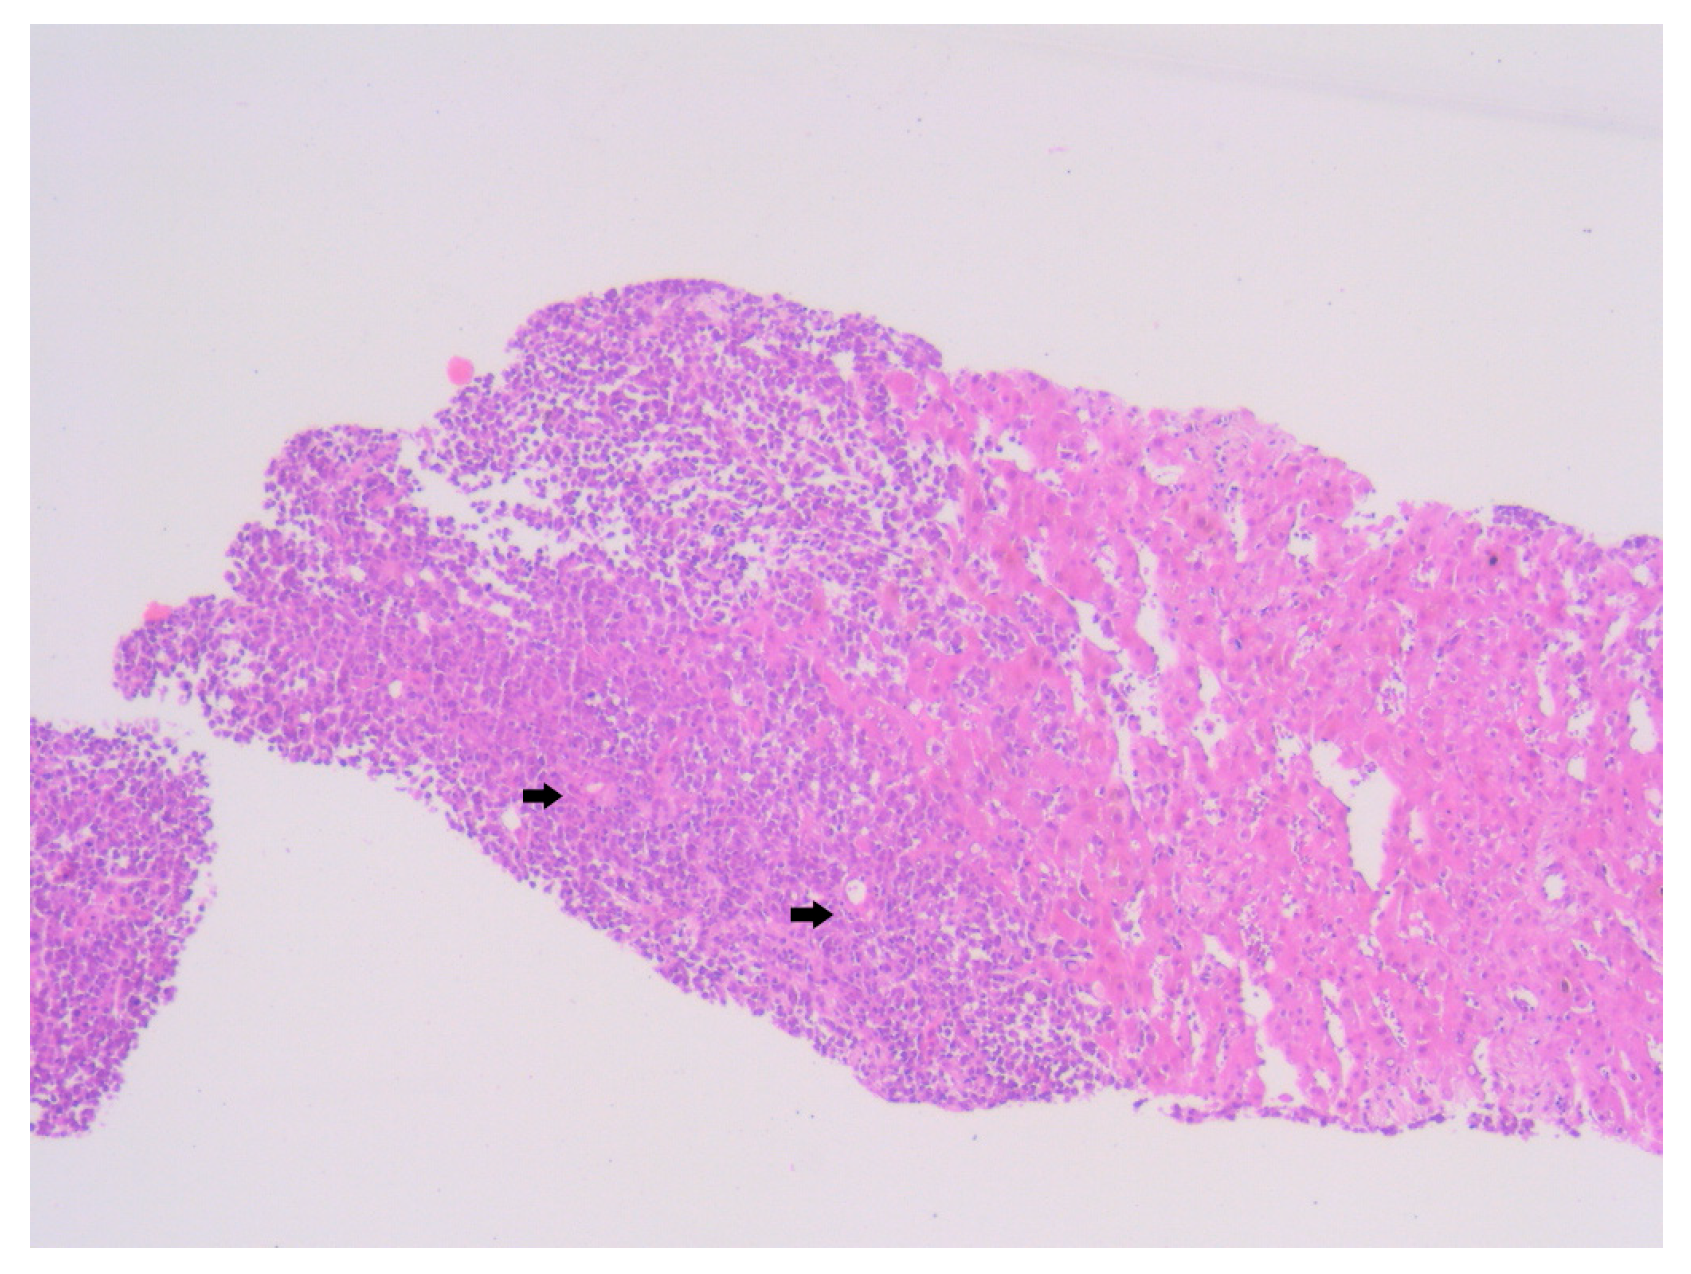

Figure 4. Hematoxylin–Eosin staining, 4× magnification (HE 4×): Biopsied fragment of hepatic parenchyma showing a tumoral proliferation located at one end, occupying approximately three high-power fields (HPFs). Arrows indicate the area of tumoral infiltration at the edge of the hepatic parenchyma.

Histopathological examination of the liver biopsy revealed fragments of hepatic parenchyma measuring 10 × 1 mm, with tumoral infiltration by small, round blue cells exhibiting indistinct cytoplasmic borders, scant eosinophilic cytoplasm and round to oval nuclei that were either hyperchromatic or euchromatic, with finely granular chromatin and absent nucleoli. Occasional mitotic figures (4 per 3 HPFs) were identified. The morphology was consistent with a small round blue cell tumor, raising differential diagnostic considerations (Figure 4, Figure 5 and Figure 6). Small round blue cell tumors involving the liver include lymphoma, plasmacytoma, metastatic small-cell lung carcinoma, high-grade neuroendocrine carcinoma, metastatic melanoma, metastatic neuroblastoma and Ewing sarcoma. In contrast to these entities, MCC usually presents with a rapidly growing cutaneous primary tumor, satellite or in-transit metastases and early involvement of regional lymph nodes, as seen in our patient. The combination of morphology (small round blue cells with scant cytoplasm and neuroendocrine features), the presence of a violaceous primary lesion on a sun-exposed site, satellite nodules, marked axillary lymphadenopathy and rapid multiorgan dissemination made MCC the most consistent diagnosis, despite the absence of immunohistochemistry. To clarify the cellular origin and reach a definitive diagnosis, correlation with clinical and paraclinical data, along with immunohistochemical testing (e.g., CK AE1/AE3, CK20, CD56, Chromogranin A, SOX10, CD20, CD3, CD138), would have been essential. The liver biopsy was obtained while the patient was hemodynamically unstable, and within hours he developed biopsy-related hemoperitoneum, shock and multiorgan failure, requiring transfer to the ICU. Due to the rapid clinical deterioration and death shortly afterward, the sample could not be processed for IHC in time, and further invasive tissue sampling was no longer ethically indicated. Nevertheless, the combination of clinical presentation (violaceous cutaneous tumor with satellite nodules), imaging (multiorgan metastases) and morphology of the liver sample (small round blue cells with neuroendocrine features) supported the presumptive diagnosis of metastatic MCC. According to the 8th edition of the American Joint Committee on Cancer (AJCC) staging system for MCC, this case corresponds to Stage IV—cT2N3M1c disease. The T2 classification applies because the primary cutaneous tumor was >2 cm. N3 reflects the presence of clinically evident, macroscopic lymph node involvement together with in-transit metastases (satellite cutaneous nodules). The M1c designation is supported by multiple visceral metastases involving the liver, spleen and suspected bone lesions on CT imaging.

The primary lesion was located on the anterior surface of the right arm, which would suggest a higher risk for cutaneous or superficial spread. However, this pattern was not observed. Instead, the patient presented with extensive visceral involvement, including the liver and spleen, bypassing the expected pathway of skin or nodal progression (Figure 4). This deviation may indicate either an aggressive tumor phenotype or possible hematogenous dissemination that override classical lymphatic pathways. The presence of both hepatic and splenic metastases, despite an upper limb origin, underlines an atypical evolution that contrasts with established metastatic models.